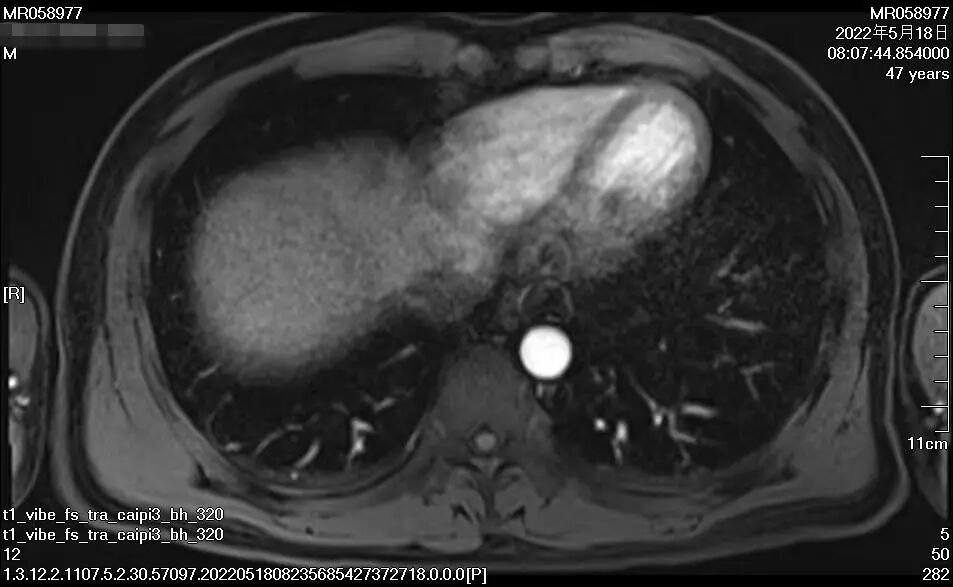

▲上圖1、2為馬先生接受治療兩月后

下圖3、4為馬先生接受治療一年后

經過整整一年的時間,16次靶向+免疫治療,近日,馬先生進行肝臟增強CT復查顯示,腫瘤相比一年前已經小了太多,“對于馬先生這種情況的肝癌患者而言,能取得這樣的療效真的是非常不容易,我們相信在接下來的進一步治療與馬先生自身積極態(tài)度下,一定能‘捷報頻傳’!”腫瘤二科主治醫(yī)師楊長命說。